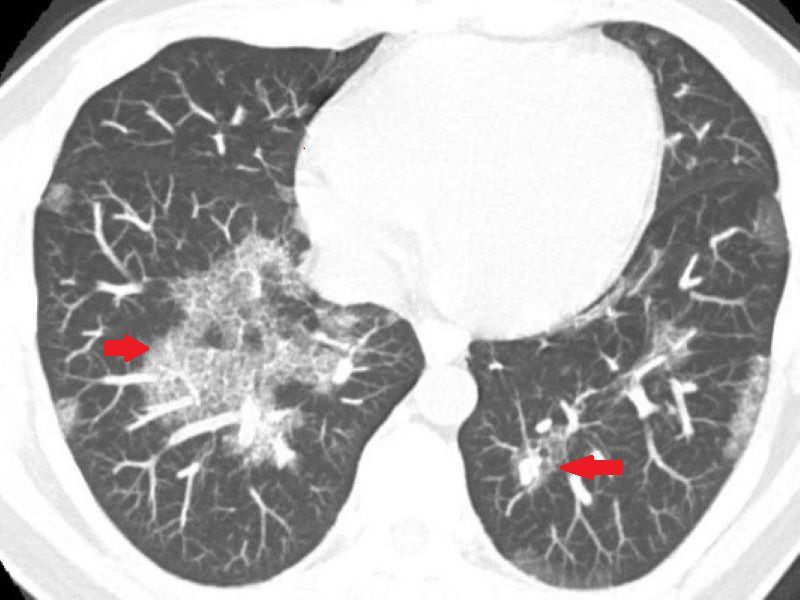

40歲的魏先生一向體格健壯,從事搬運工作多年,體能不輸年輕人。然而,近兩年來他逐漸感覺力不從心,肺活量明顯下降,時常出現間歇性暈眩,甚至有數次在搬運重物時,突然吸不到氣,胸口像是被重物壓住般喘不過氣來。近期他更在平時活動中出現背部劇烈疼痛,這才引起他的警覺,前往診所檢查,意外發現肺部有大片白影,隨即轉診至台北慈濟醫院胸腔內科。藍冑進主任與醫療團隊全面評估,電腦斷層初步研判為肺部慢性發炎,但進一步的支氣管鏡檢查卻顯示氣道清晰無異常,連同細菌與黴菌等各項培養檢查也均為陰性,病因成謎,只能密切追蹤病況,但三個月後卻發現雙肺白影惡化,最後,魏先生接受電腦斷層導引下的肺部穿刺切片,確診為極為罕見的肺部蛋白質沉積症(Pulmonary Alveolar Proteinosis, PAP)。

魏先生的胸部影像檢查有大片白影。